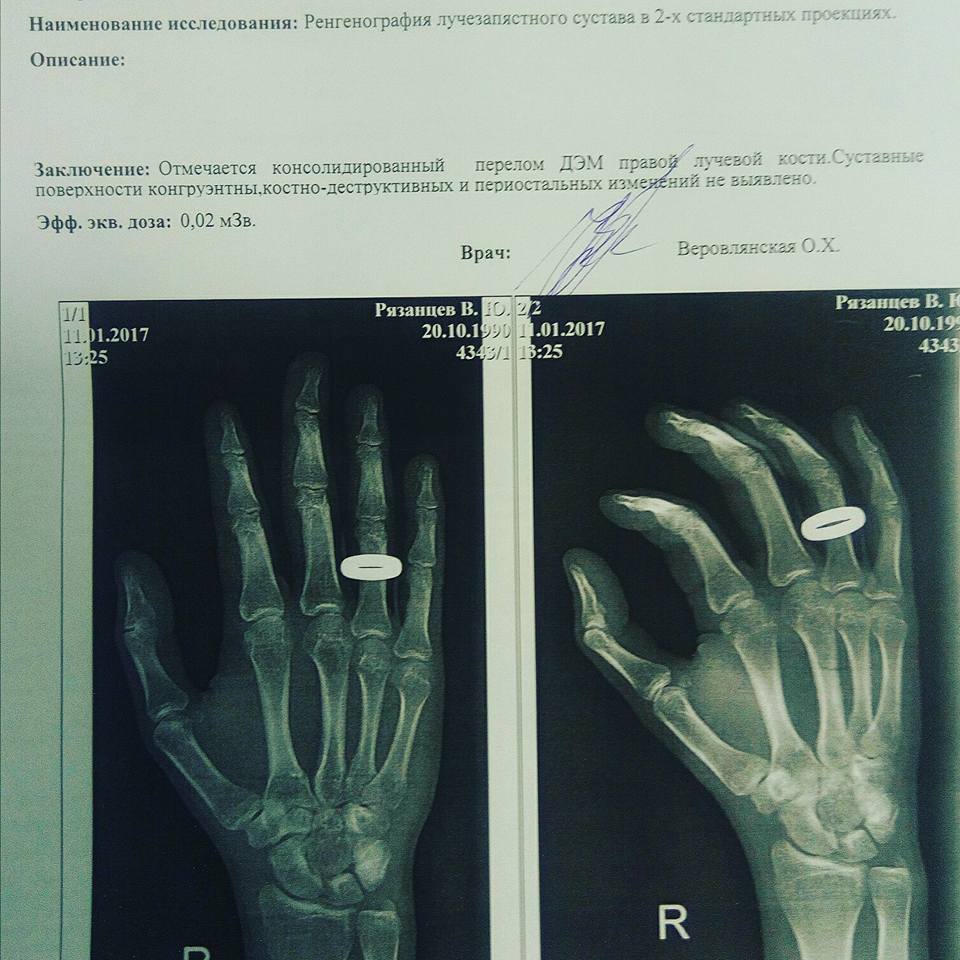

“В поликлинике рентген показал, что у меня есть перелом кисти правой руки. Четыре года назад у меня в этом же месте была травма. Врачи говорят, что, возможно, после избиения старый перелом дал о себе знать. Рука сейчас не сгибается, не разгибается, а общее самочувствие является неудовлетворительным”, - добавил Рязанцев.

В заключении врачей говорится о том, что у Рязанцева диагностирован перелом. Заключение сделано на основе рентгеновского снимка. “Отмечается консолидированный перелом ДЭМ правой лучевой кости”, - говорится в заключении, копия которого имеется в распоряжении “Кавказского узла”.